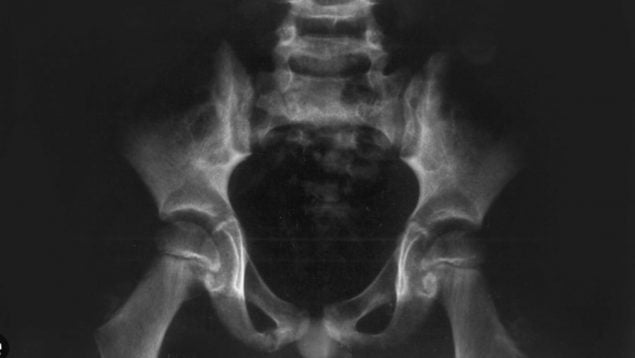

La osteomielitis púbica es una afección poco frecuente y poco conocida fuera del ámbito clínico especializado. El hueso púbico forma parte de la pelvis y está implicado en la estabilidad del tronco y la biomecánica de la marcha; una infección en esta área puede manifestarse con dolor en la parte baja del abdomen o en la región inguinal y con dificultad para caminar o mantener fuerza normal en las piernas.